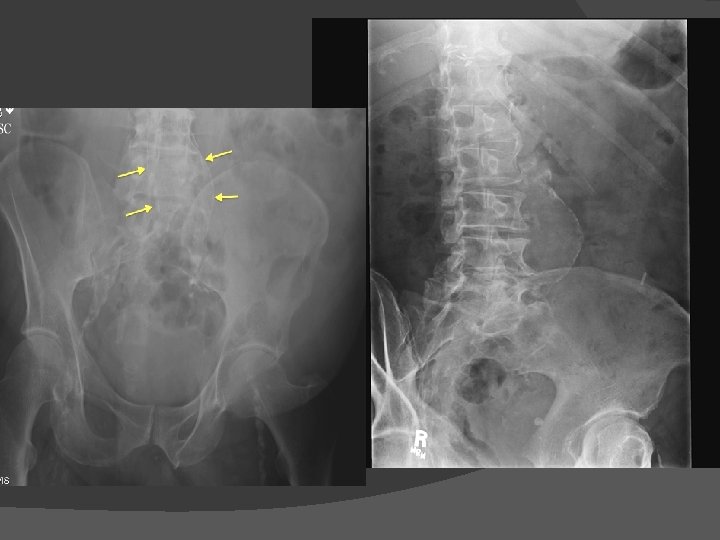

Diagnostic imaging � Abdonimal USG �Non-invasive, inexpensive, free of radiation and contrast free � CT angiogram �More accurate than USG �Relationship of AAA with other vessels �Coexisting mural thrombosis, calcification, occlusive atherosclerosis �Enhance visualization of AAA before EVAR � MRA- Magnetic resonance angiography

Screening Done using USG � Incidence � 1 per 1000 in males over 60 years of age � 7 per 1000 in males over 70 years of age � 10% in males over 60 years of age with risk factors like smoking, F/H, HTN, atherosclerosis � Impact of screening-early diagnosis � 50% reduction in rupture cases � 50% reduction in overall aneurysm related mortality. � In females controversial with no clear survival benefit (MASS � study)